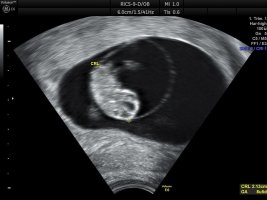

Så liten og perfekt liten perle

Her er bamsemumset vårt, med bankende hjerte

For en følelse! For en glede! Lille venn har navlesnoren i morkaken nå så den mest kritiske fasen var over sa jordmor. Alt så helt supert ut

Hun målte lille til 2,13 cm og nøyaktig 8+5 i dag, som er nøyaktig samme dagen jeg har